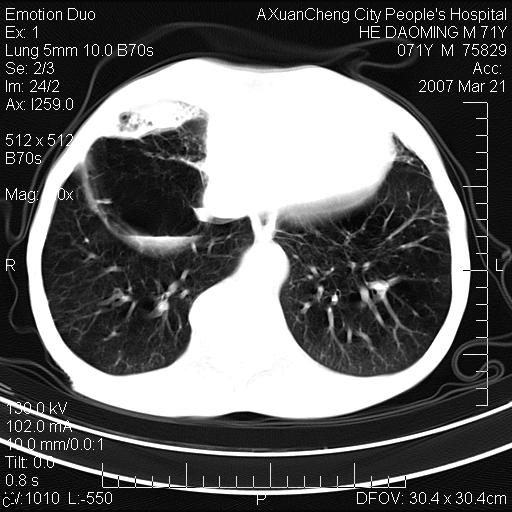

标题: CT7269:[原创] 咳嗽,咳痰,大家讨论右肺病变的部位

右侧相当于叶间软组织样密度ct值约50hu,请大家讨论是什么性者病变

考虑:慢性支气管炎合并全小型肺气肿、肺大泡、间质纤维化、感染,右斜裂积液。

考虑慢支,肺气肿,肺大泡,间质纤维化;右侧斜裂液气胸考虑(可能因为肺大泡破裂破入斜裂所致).

考虑病变以右上中肺多发肺大泡为主并感染。请结合临床考虑慢支肺气肿,肺心病。

考虑:慢性支气管炎合并右侧全小型肺气肿、肺大泡并感染、双肺间质纤维化,右斜裂积液。

如果患者变化一下体位扫描可分辨液平与斜裂的关系。